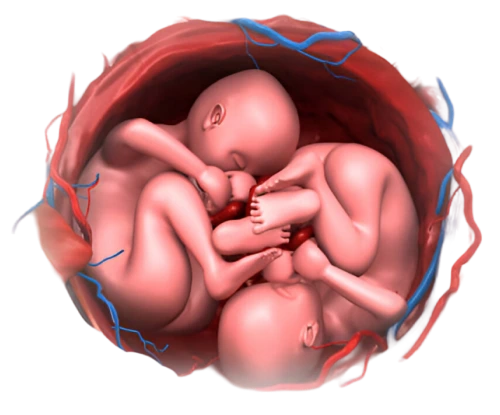

- Multiple pregnancies (twins, triplets, or more): Higher chances of preterm birth or pregnancy complications.

- Multiple Pregnancies (Twins or More)

Bed rest is sometimes recommended for women with certain high-risk conditions like preeclampsia or multiple pregnancies. However, not all high-risk pregnancies require bed rest. Your doctor will determine if it’s necessary based on your specific condition.